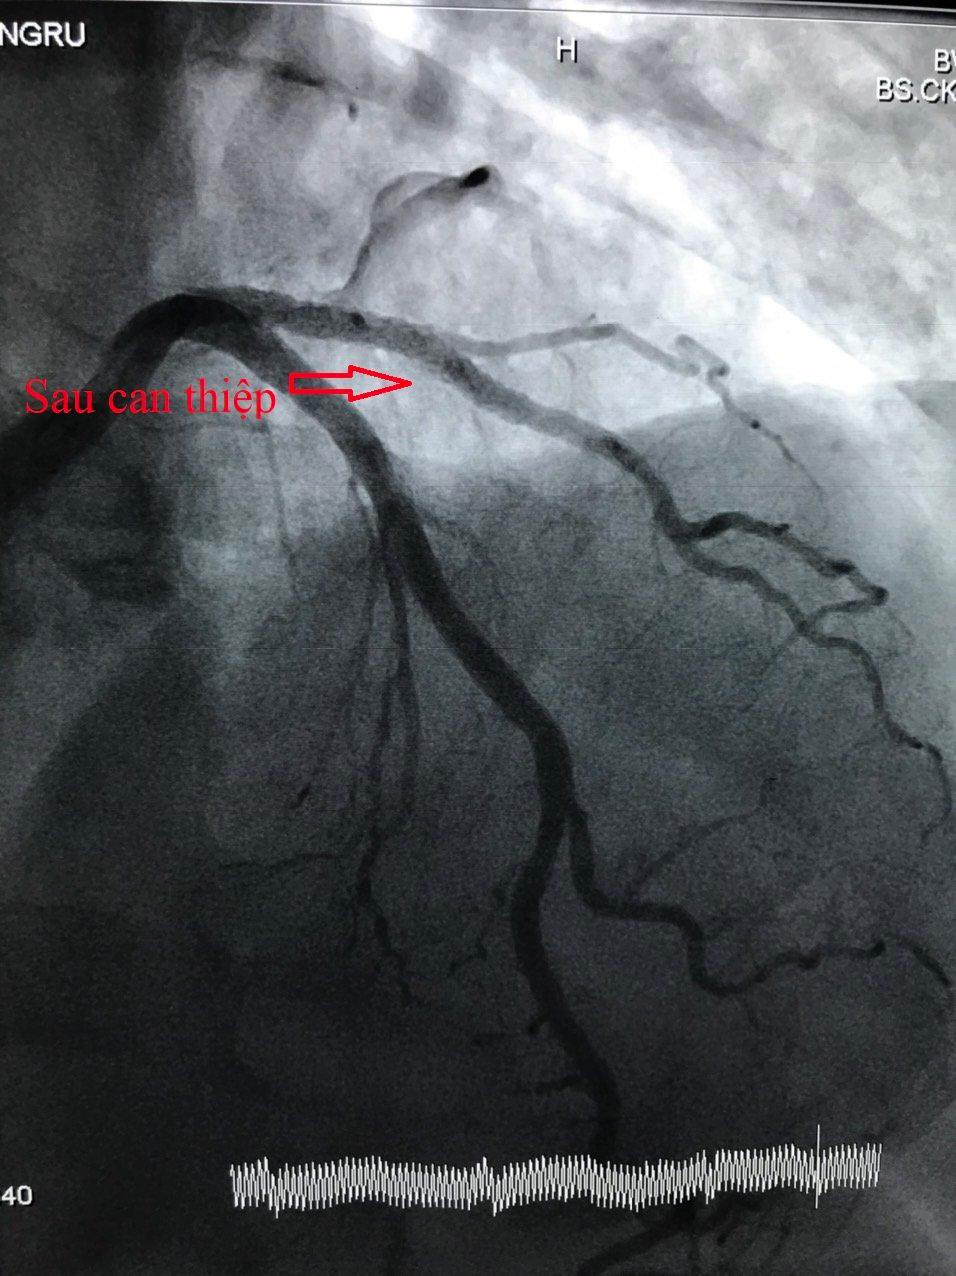

Sau can thiệp, bệnh nhân tỉnh, mạch, huyết áp ổn định, giảm đau ngực nhiều và tiếp tục điều trị tại Khoa Tim mạch can thiệp .

Hình ảnh mạch vành sau can thiệp |